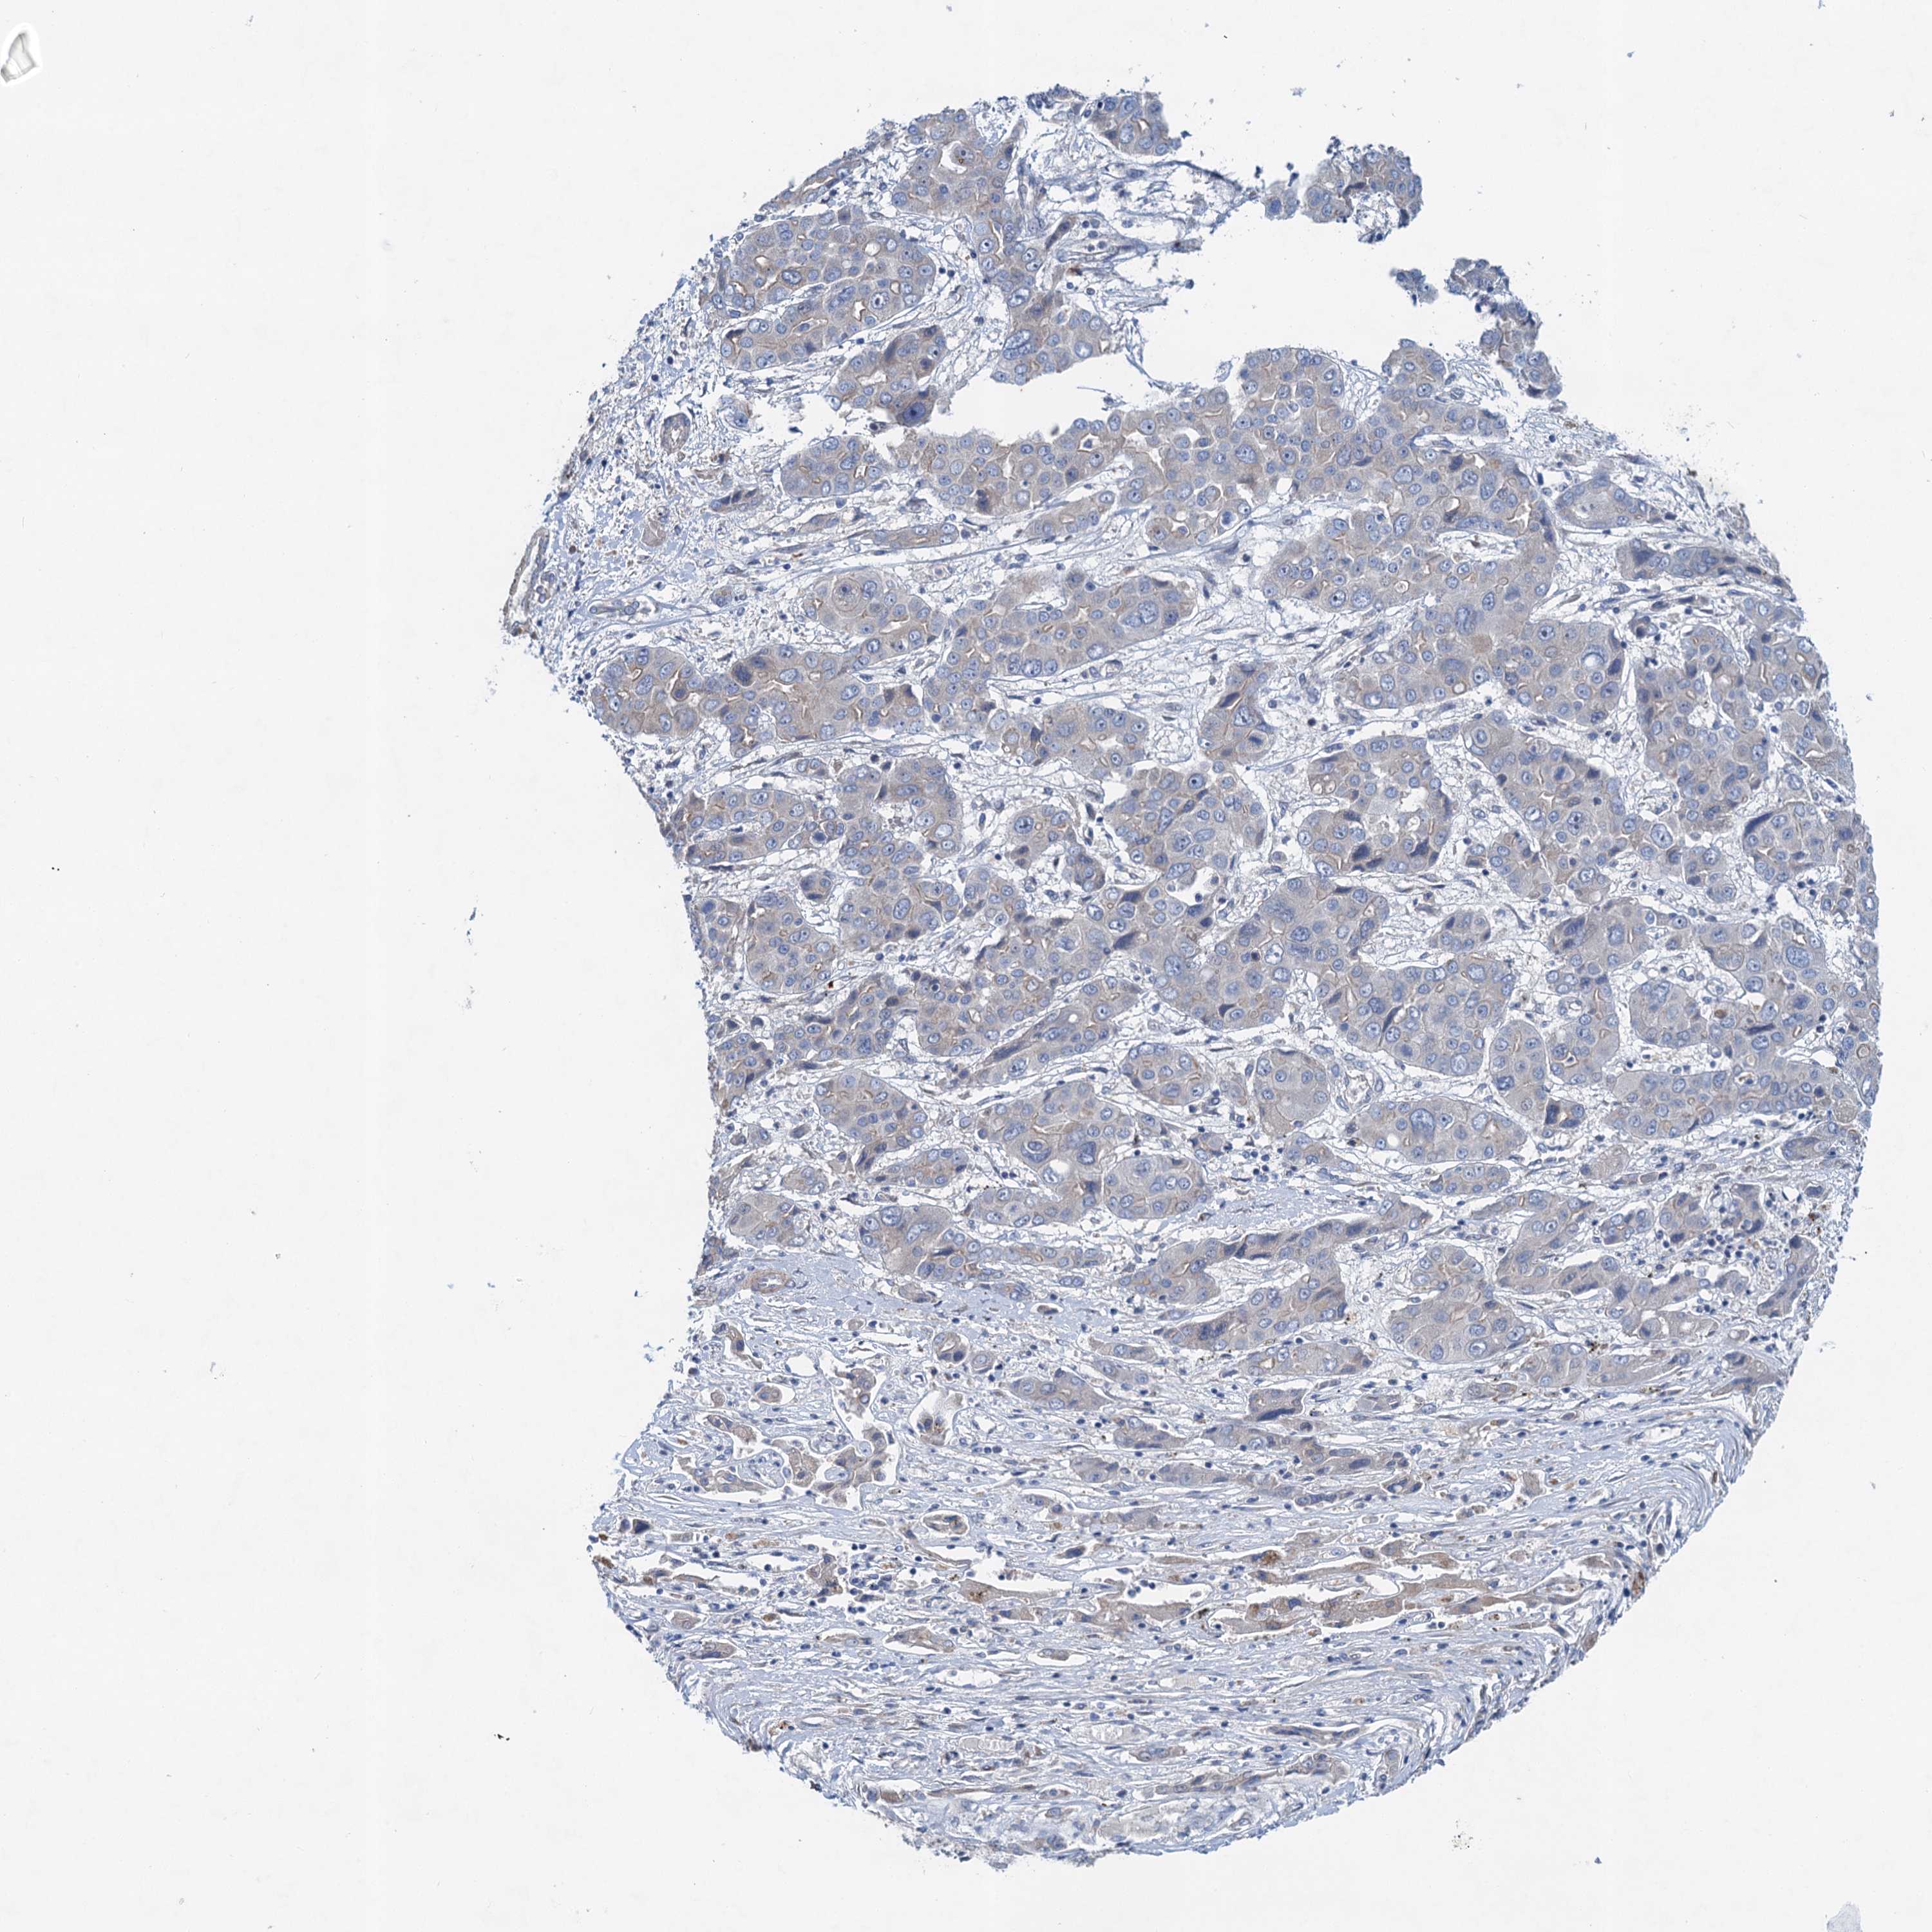

LIVER CANCER - Protein expressioni

A mouse-over function shows sample information and annotation data. Click on an image to view it in a full screen mode. Samples can be filtered based on level of antibody staining by selecting one or several of the following categories: high, medium, low and not detected. The assay and annotation is described here.

Note that samples used for immunohistochemistry by the Human Protein Atlas do not correspond to samples in the TCGA dataset.

Antibody stainingi

Antibody staining in the annotated cell types in the current human tissue is reported as not detected, low, medium, or high, based on conventional immunohistochemistry profiling in selected tissues. This score is based on the combination of the staining intensity and fraction of stained cells.

Each image is clickable and will lead to virtual microscopy that enables deeper exploration of all samples and also displays staining intensity scores, fraction scores and subcellular localization as well as patient and tissue information for each sample.

Antibody HPA039730

Antibody HPA040385

Staining

High

Medium

Low

Not detected

Intensity

Strong

Moderate

Weak

Negative

Quantity

>75%

75%-25%

<25%

None

Location

Nuclear

Cytoplasmic/membranous

Cytoplasmic/membranous,nuclear

Cholangiocarcinoma

Carcinoma, Hepatocellular, NOS